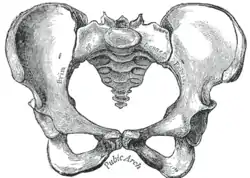

![]() Male pelvis |

![]() Female pelvis |

| Comparison between an android (left) and a gynecoid pelvis (right). | |